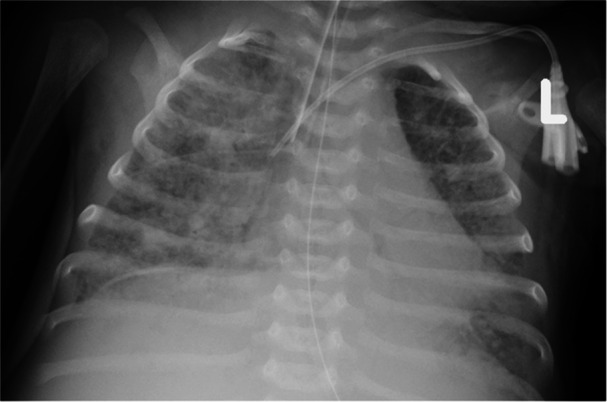

Background: We report a 1-month-old infant admitted with fever, dyspnea, and desaturation after an unmonitored pregnancy in a migrant family. The patient rapidly required mechanical ventilation. Laboratory parameters were markedly elevated, suggesting an infectious etiology.

Methods: The clinical course is described with emphasis on diagnostic challenges, including imaging, laboratory findings, and the stepwise process of differential diagnosis.

Results: After common etiologies were excluded, rarer causes were considered. The final diagnosis was established through integration of clinical assessment, radiological imaging, laboratory data, and microbiological testing.

Conclusion: In neonates with fever and respiratory distress, RSV bronchiolitis is usually the first consideration. If excluded, clinicians must remain alert to less frequent etiologies. This case underscores the importance of a broad differential diagnosis in infants with acute respiratory compromise.